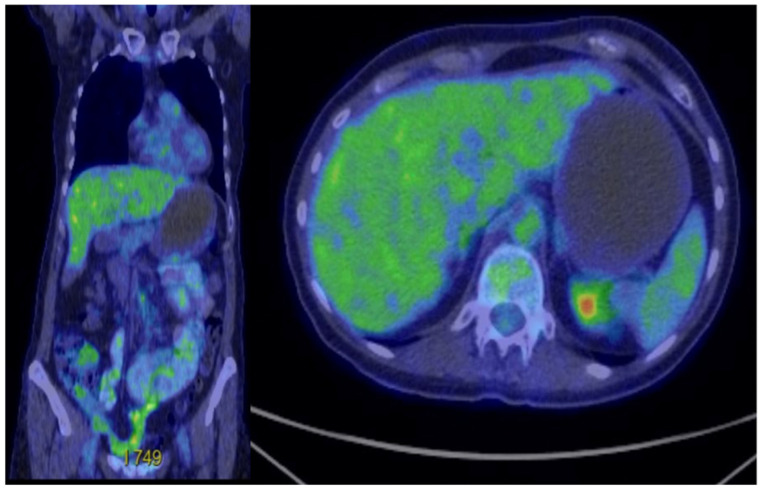

背景:胃肠道神经外胚层肿瘤(GNET),也称为胃肠道透明细胞肉瘤(CCS),是一种罕见的神经嵴源性恶性肿瘤,其特征为EWSR1-ATF1或EWSR1-CREB1融合。由于其罕见性,证据有限,没有标准管理的既定指南。GNET具有侵袭性,局部复发、转移和死亡率高。病例介绍:我们报告了一名46岁的女性,她有胃肠道癌症家族史,于2020年被诊断出患有肠道GNET。她接受了段性肠切除术作为多模式治疗的第一步。经过三年的随访,她出现了肝脏和腹膜转移。2023年11月,她开始联合使用抗vegf酪氨酸激酶抑制剂cabozantinib和免疫检查点抑制剂nivolumab。患者病情稳定18个月,耐受性良好,无不良事件发生。肿瘤的分子分析显示EWSR1-CREB1融合,支持选择靶向治疗和免疫治疗作为首选治疗方法。结论:免疫治疗和靶向治疗显示出GNET/CCS治疗的前景,但缺乏临床标准,证据主要来自病例报告。需要更多的数据来确定这种非常罕见疾病的最佳治疗顺序和组合。

Background: Gastrointestinal neuroectodermal tumour (GNET), also known as clear cell sarcoma (CCS) of the gastrointestinal tract, is a rare neural crest-derived malignancy characterized by EWSR1-ATF1 or EWSR1-CREB1 fusions. Due to its rarity, there is limited evidence and no established guidelines for standard management. GNET is aggressive, with high rates of local recurrence, metastasis, and mortality. Case Presentation: We report the case of a 46-year-old woman with a family history of gastrointestinal cancers who was diagnosed in 2020 with an intestinal GNET. She underwent a segmental enterectomy as the first step of multimodal therapy. After three years of follow-up, she developed hepatic and peritoneal metastases. In November 2023, she began combined therapy with the anti-VEGF tyrosine kinase inhibitor cabozantinib and the immune checkpoint inhibitor nivolumab. The patient has maintained stable disease for 18 months with good tolerance and no adverse events. Molecular analysis of the tumour, which showed an EWSR1-CREB1 fusion, supported the selection of targeted therapy and immunotherapy as the preferred treatment approach. Conclusions: Immunotherapy and targeted therapy show promise for GNET/CCS treatment, but clinical standards are lacking, and evidence comes primarily from case reports. Additional data are needed to determine the best sequence and combination of therapies for this very rare disease.